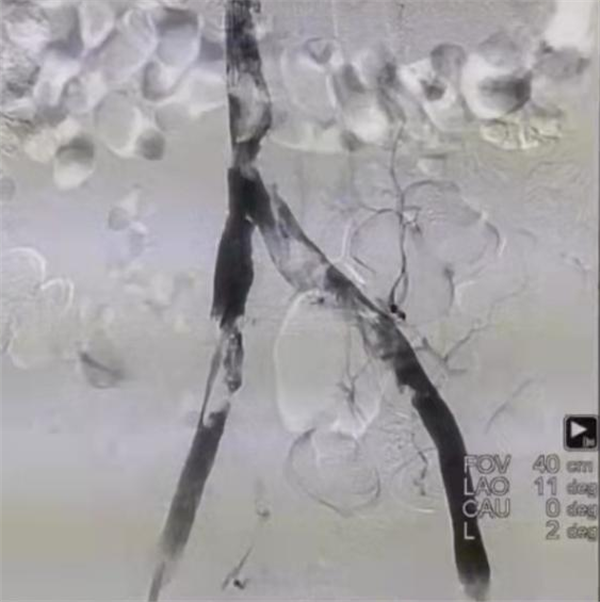

术前造影

患者病情危重,呼吸机辅助呼吸,入住重症监护室,既往患有“格林巴利综合征”,四肢活动障碍,呼吸衰竭,双肺叶肺不张,大量胸腔积液。鉴于该患者病情极危重,而且情况复杂,马建仓教授带领团队,反复讨论,制定方案。由于患者检查结果显示隐血阳性,凝血因子异常,纤维蛋白原低,所以导管接触性溶栓风险极大,所以吸栓就成为患者最为恰当的治疗方案,而吸栓的产品多样,在以往的吸栓手术中常用Anjoget吸栓装置,但是它会导致红细胞破坏,溶血的可能。而最新的AcoStream吸栓装置简单安全,持续稳定的真空负压输出,简单安全,不损伤血管,且高流量抽吸,满足下肢深静脉大负荷血栓清除需求,术中并发症少,所以最终决定使用最新的AcoStream进行下腔静脉吸栓。马建仓教授带领团队凭借扎实的专业基础,以及丰富的治疗经验,为患者成功实施我省首例局麻下AcoStream下腔静脉吸栓术。

术中吸栓过程

该方案从计划到实施,一切都在既定范围内顺利开展,为患者争取了更多的治疗时间。术后效果明显,患者术前腿围左腿34cm,右腿33cm,术后3小时左右腿围均为32cm,术后16小时患者腿围左腿30cm,右腿30.5cm,肿胀程度明显缓解。抽吸除大量新鲜血栓,约30ml,再次造影原布满血栓,无血流的血管内血流立刻恢复,治疗效果立竿见影。